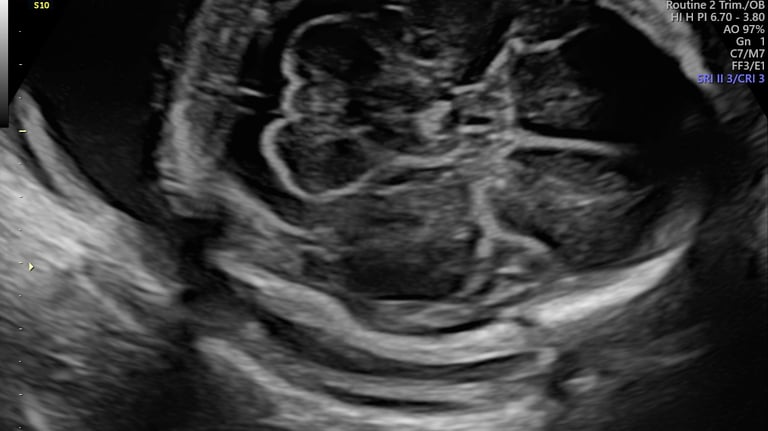

ecografía morfológica

18 - 24 semanas

ecocardiografía fetal

neurosonografía fetal